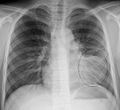

A chest X-ray showing a very prominent wedge shaped pneumonia in the right lung. | |